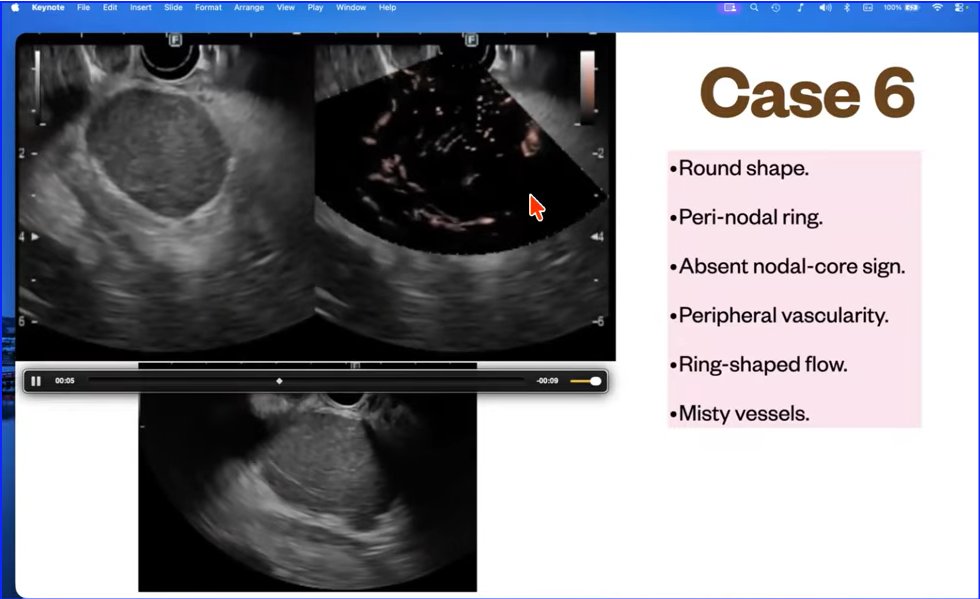

Lymph Node exam - EUS @ASGEendoscopy @drkeithsiau @DouglasAdlerMD @EUSandEndoscopy @NeethiDasu @PrabinSharmaMD

Lymph Node characteristics Findings on EUS exam

Pink Highlighted LN--> Malignant

Yellow Highlighted LN--> Benign

EUS by by Dr Vikram Bhatia

Source youtu.be/XBY448TO2WU?si… #EUS #GItwitter #LN #Malignancy